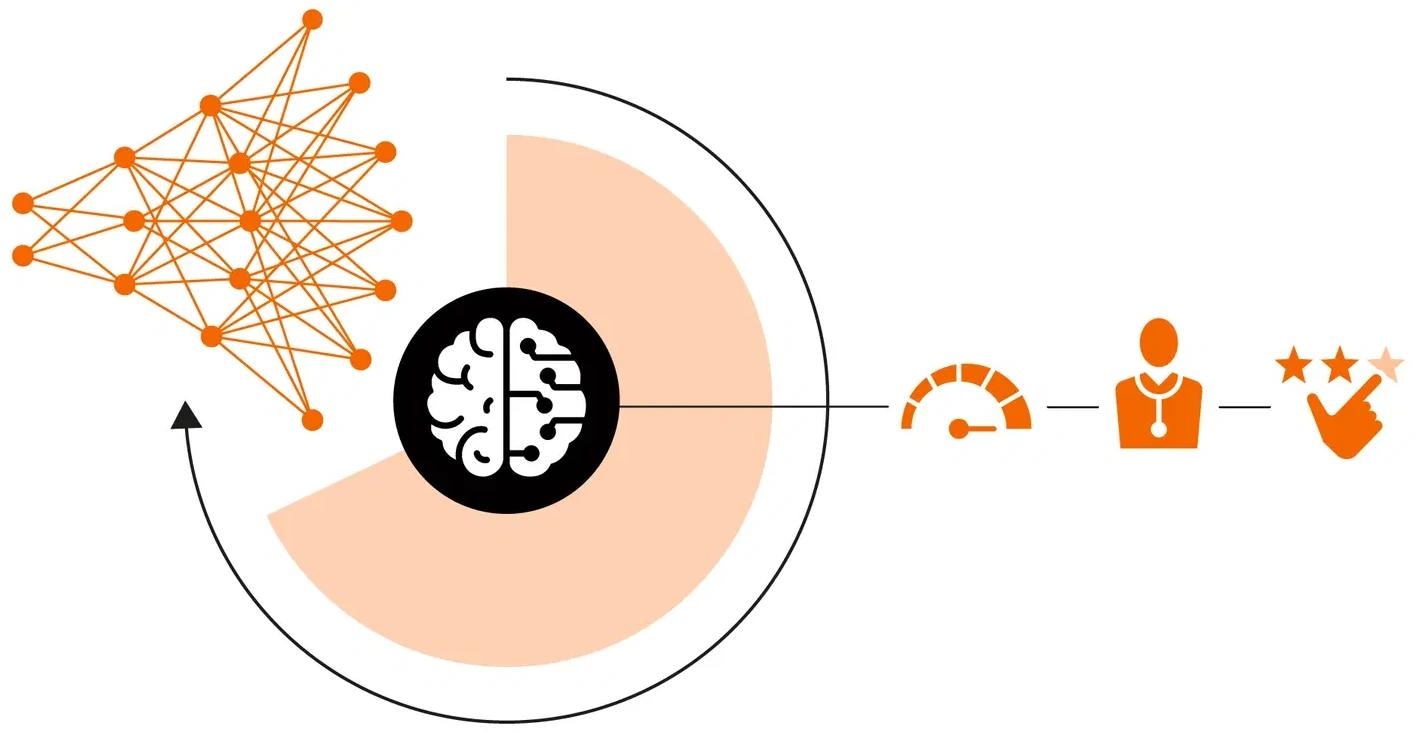

Deep Resolve

Deep Resolve, an AI-driven image reconstruction technology, speeds up MR scans, thereby making them quicker than ever before.

Deep Resolve, an AI-powered image reconstruction technology, takes advantage of convolutional neural networks to accelerate MR scans. Faster scans boost workflow efficiency while improving the patient experience. Deep Resolve’s raw data-to-image reconstruction and fast acquisition change the MRI game, helping to generate actionable insights that can be diagnostically relevant – faster than ever before.